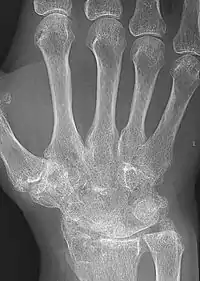

X-rays of the hands and feet are generally performed when many joints affected. In RA, there may be no changes in the early stages of the disease or the x-ray may show osteopenia near the joint, soft tissue swelling, and a smaller than normal joint space. As the disease advances, there may be bony erosions and subluxation. Other medical imaging techniques such as magnetic resonance imaging (MRI) and ultrasound are also used in RA.[20][68]